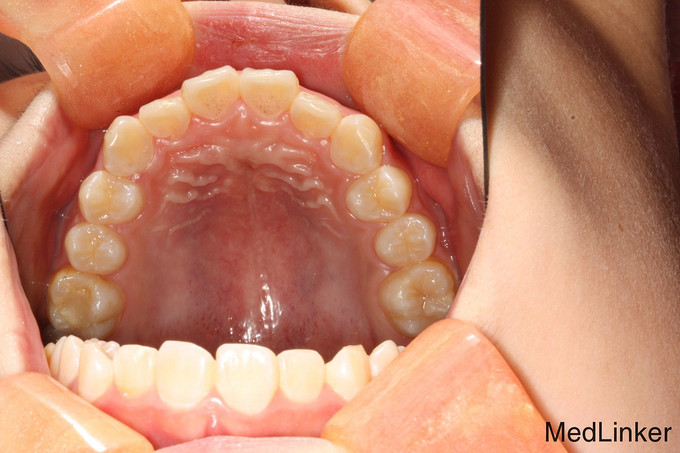

儿童牙齿矫正

12岁儿童,无过敏史,因牙列不齐,需要做正畸矫正术